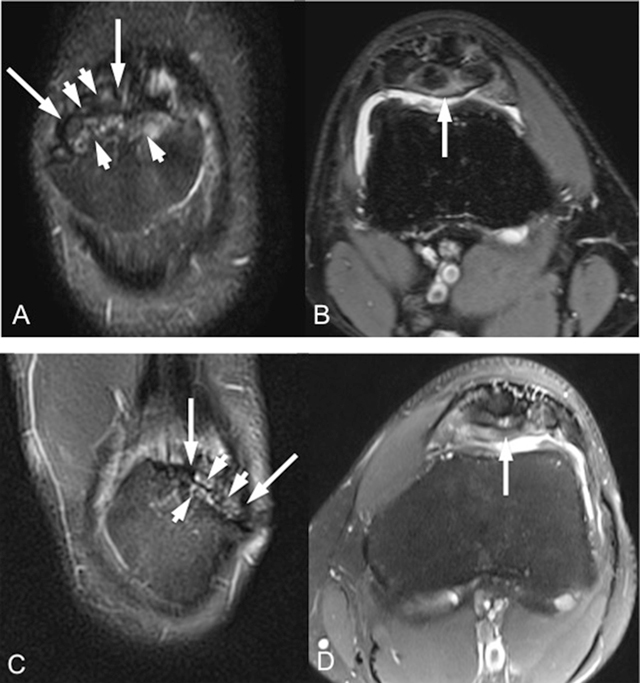

Figure 1

Coronal fat-saturated T2-weighted (A, C) and axial fat-saturated proton-density-weighted (B, D) MR images (respectively for right and left knee) show bilateral multipartite patella variation (long arrows) with bone marrow edema-like signal changes within the bony fragments (short arrows).